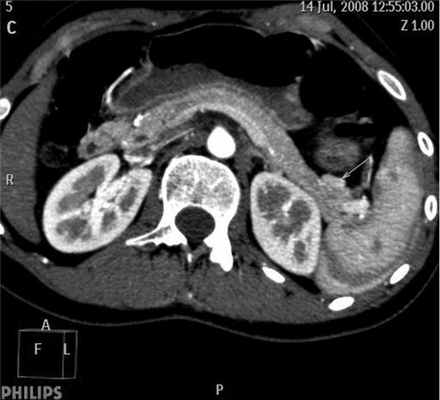

При УЗИ брюшной полости патологических изменений не выявлено. УЗИ щитовидной железы: узел размером 18×13 мм в правой доле, неоднородной структуры. Больная консультирована эндокринологом, рекомендована диагностическая пункция узла в плановом порядке после оперативного вмешательства на ПЖ. При эндоскопическом УЗИ радиальным датчиком заподозрено очаговое образование в области хвоста ПЖ до 10 мм в диаметре. МД-СКТ брюшной полости и головного мозга: гиперденсное образование по переднему контуру хвоста ПЖ размером 16×10 мм (рис. 2), Рисунок 2. Мультидетекторная спиральная компьютерная томограмма больного К. Инсулинома хвоста поджелудочной железы (стрелка). размер аденомы гипофиза 10 мм. МРТ брюшной полости: патологических изменений не выявлено.